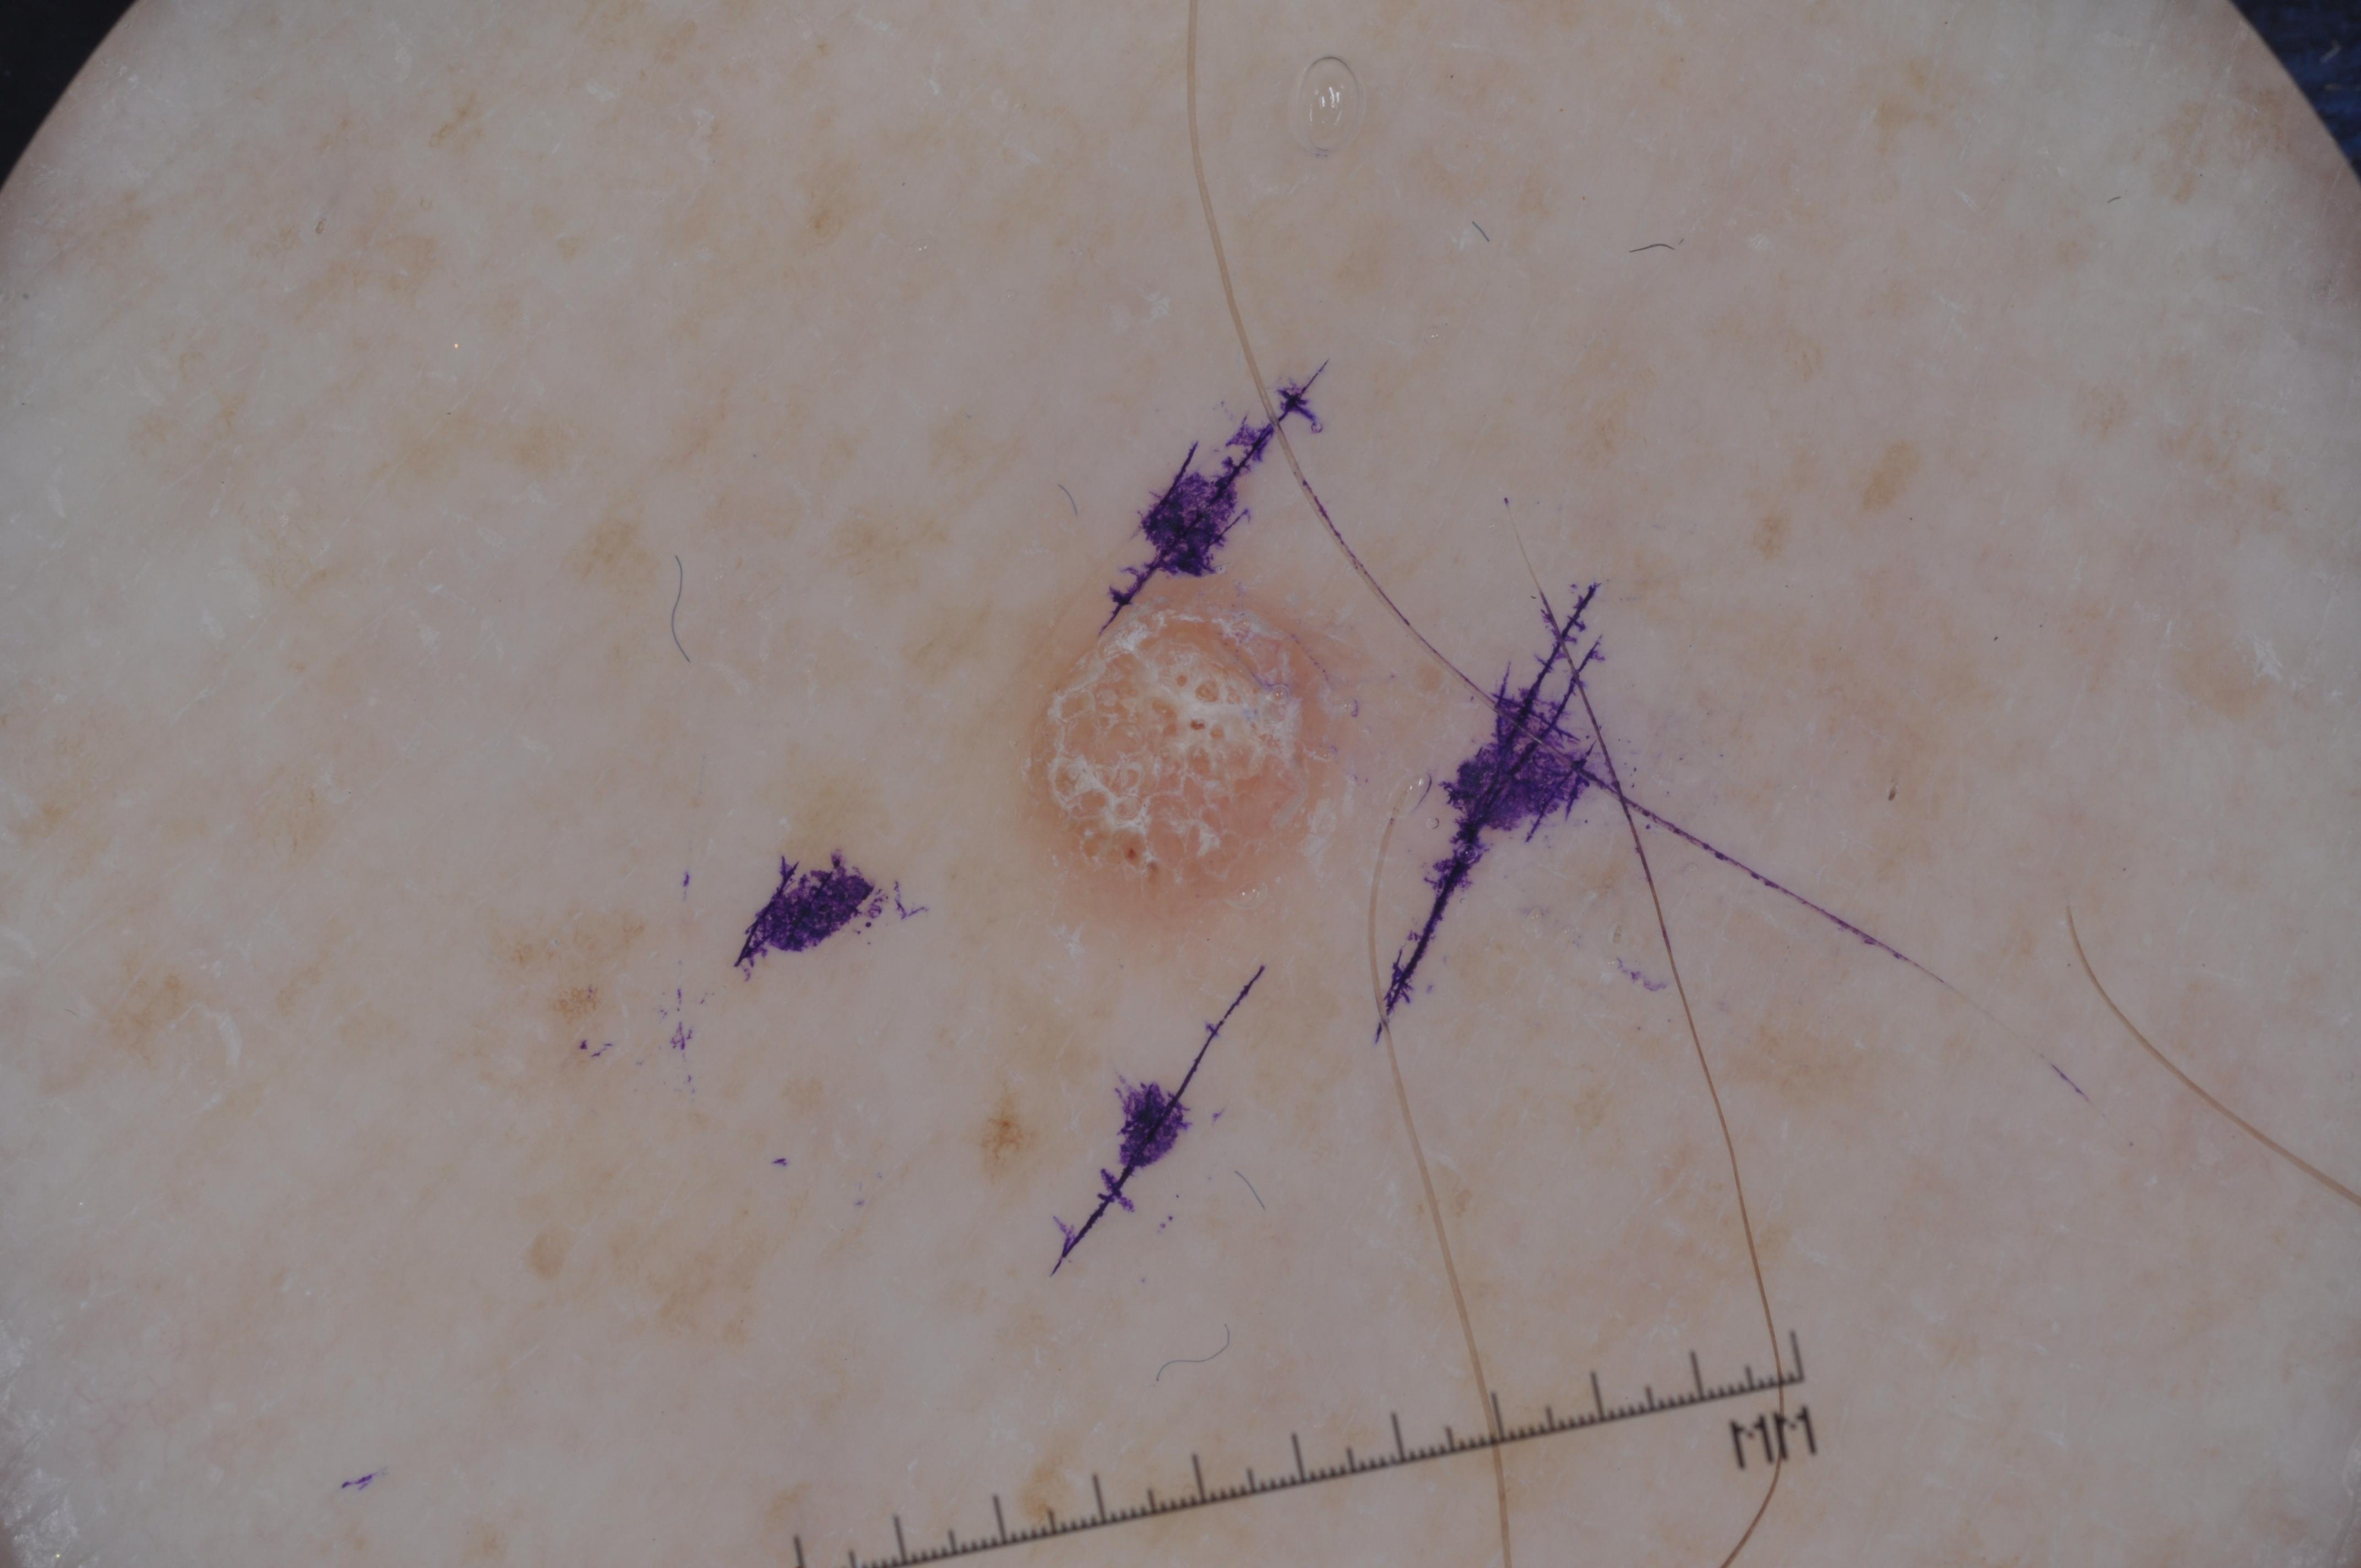

{

"age_approx": 55,

"anatom_site_general": "head/neck",

"concomitant_biopsy": true,

"dermoscopic_type": "contact non-polarized",

"diagnosis_1": "Benign",

"diagnosis_2": "Inflammatory or infectious diseases",

"diagnosis_3": "Verruca",

"diagnosis_confirm_type": "histopathology",

"image_type": "dermoscopic",

"lesion_id": "IL_0853918",

"melanocytic": false,

"sex": "male"

}